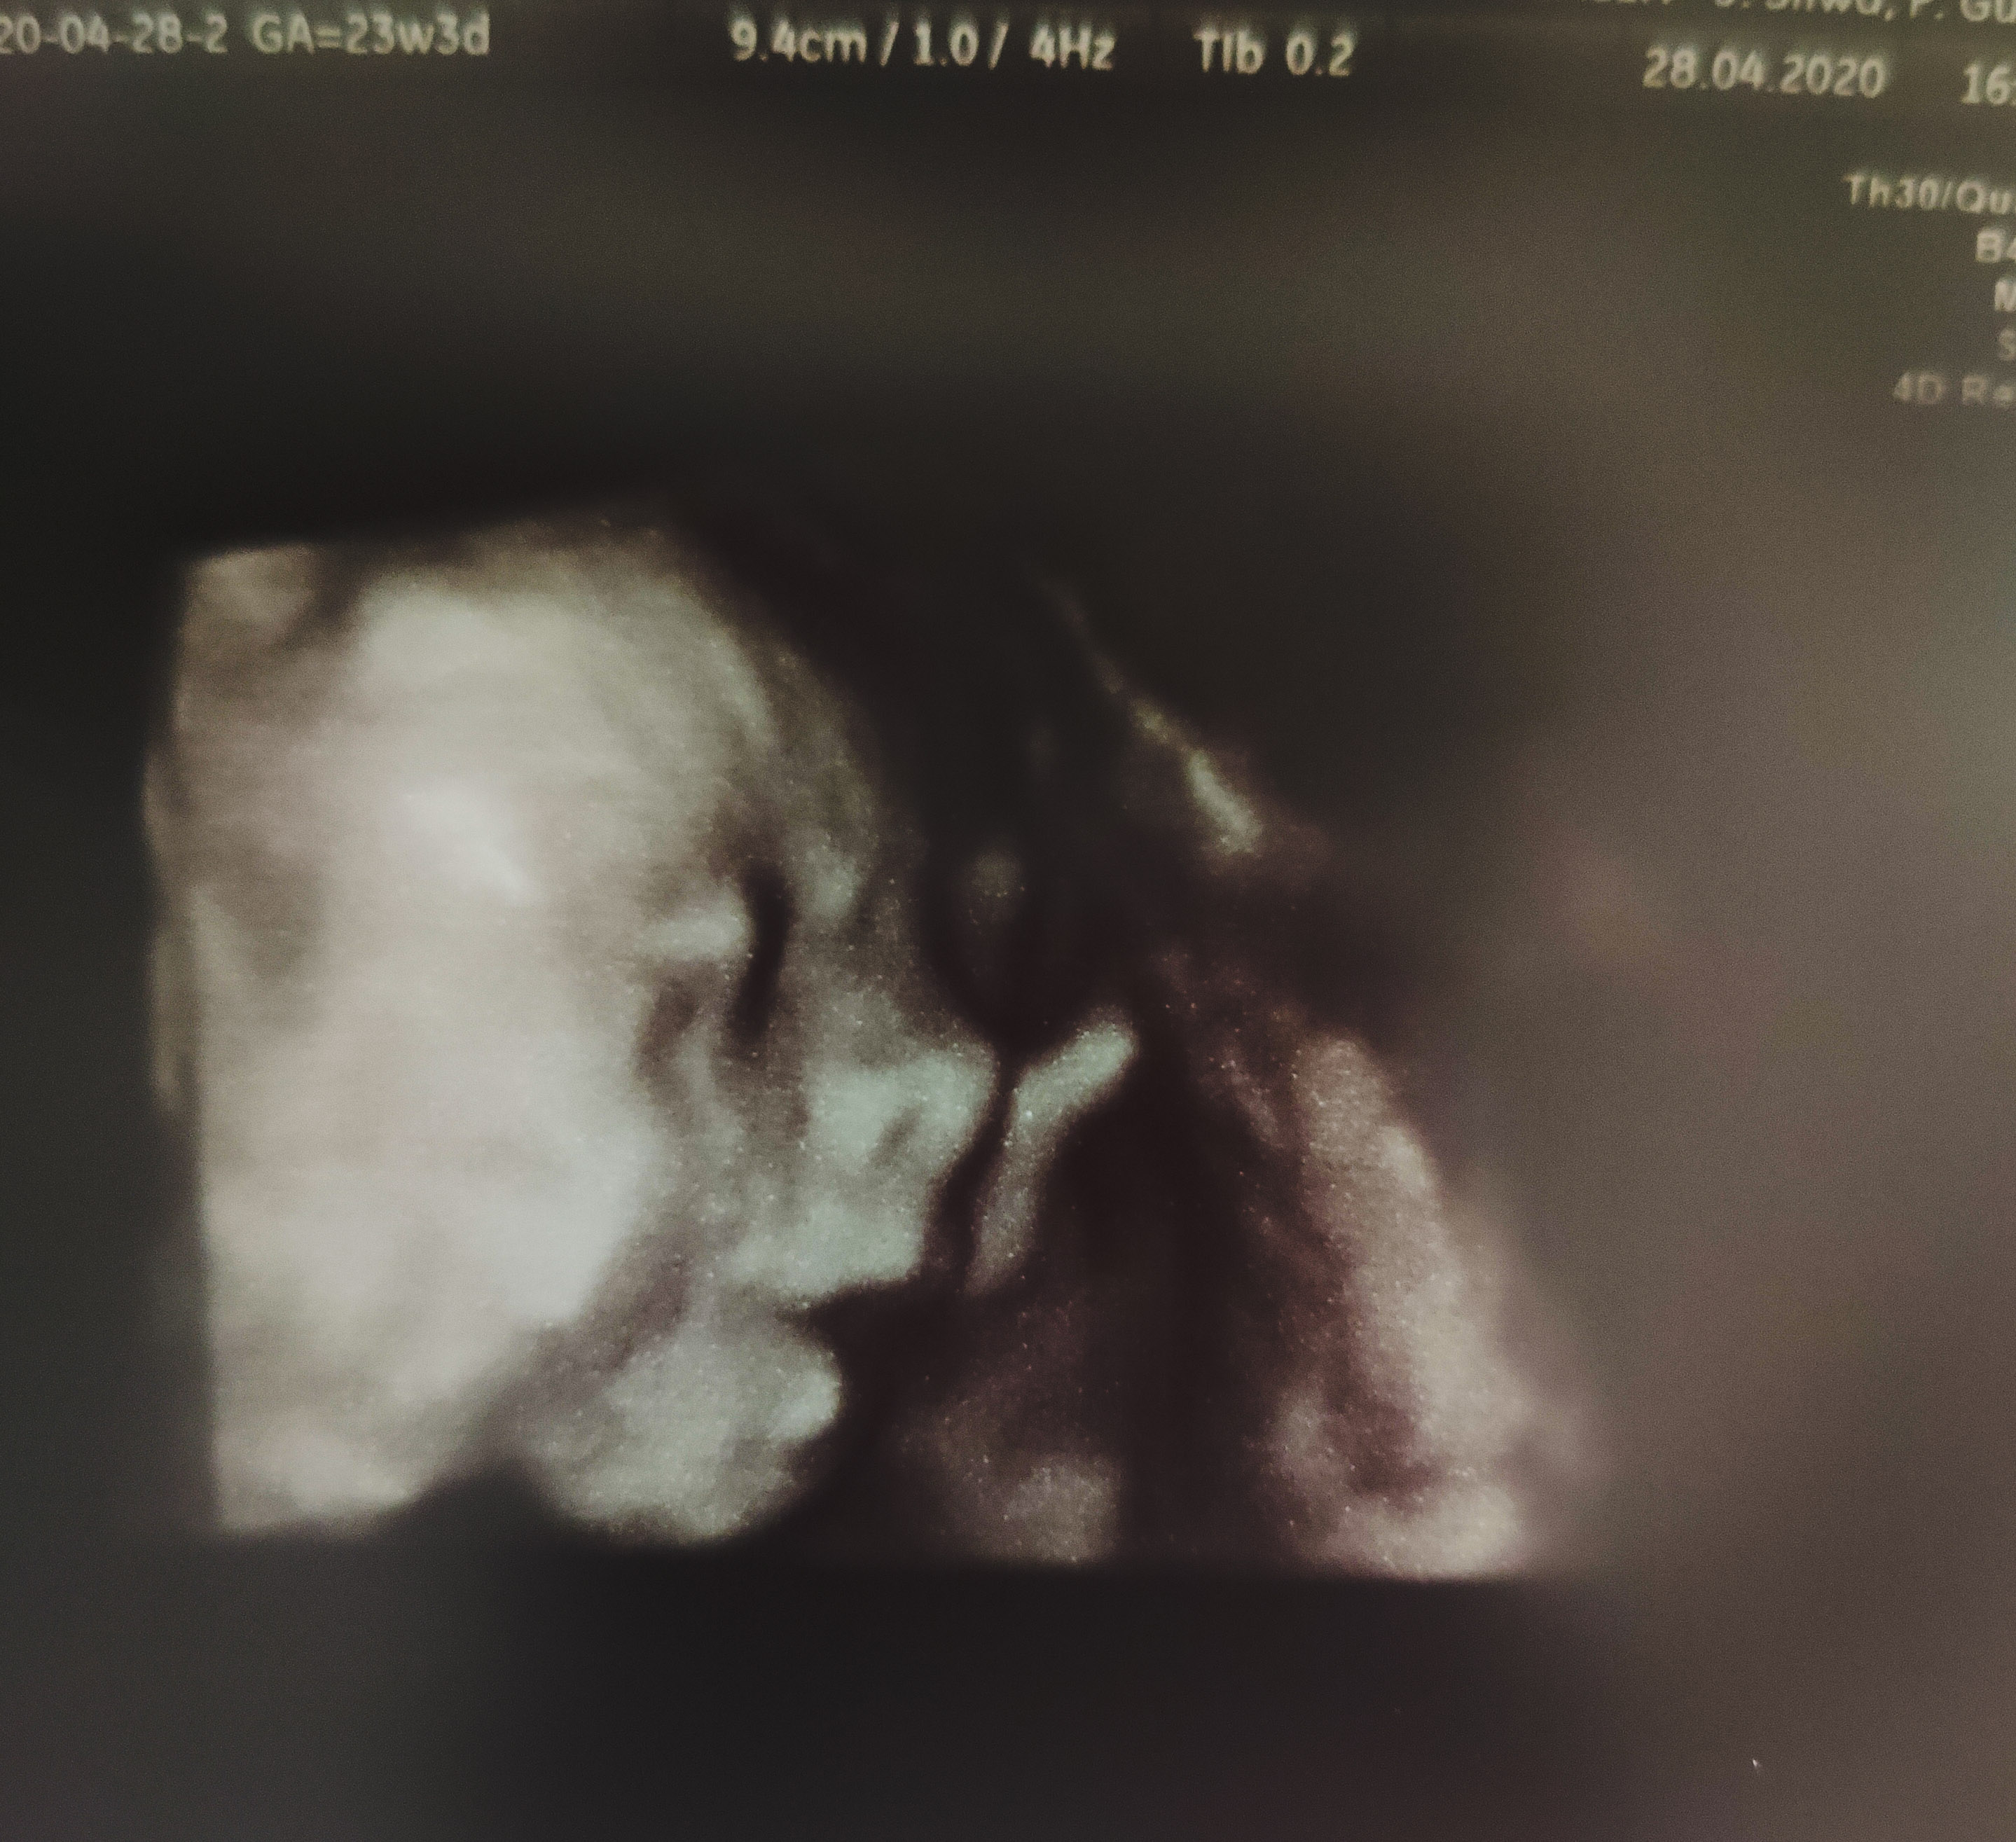

U mnie dobrze, aktualnie jestem 25Tc+4, połowa 6 miesiąca, w przyszłym tygodniu mam wizytę, ostatnio w 23Tc+3 synuś ważył 684gramy więc rośniemy.

Załączniki

• PSX_20200510_153026.jpg

PSX_20200510_153026.jpg

772 KB · Wyświetleń: 99

• PSX_20200428_173022.jpg

PSX_20200428_173022.jpg

1 MB · Wyświetleń: 102